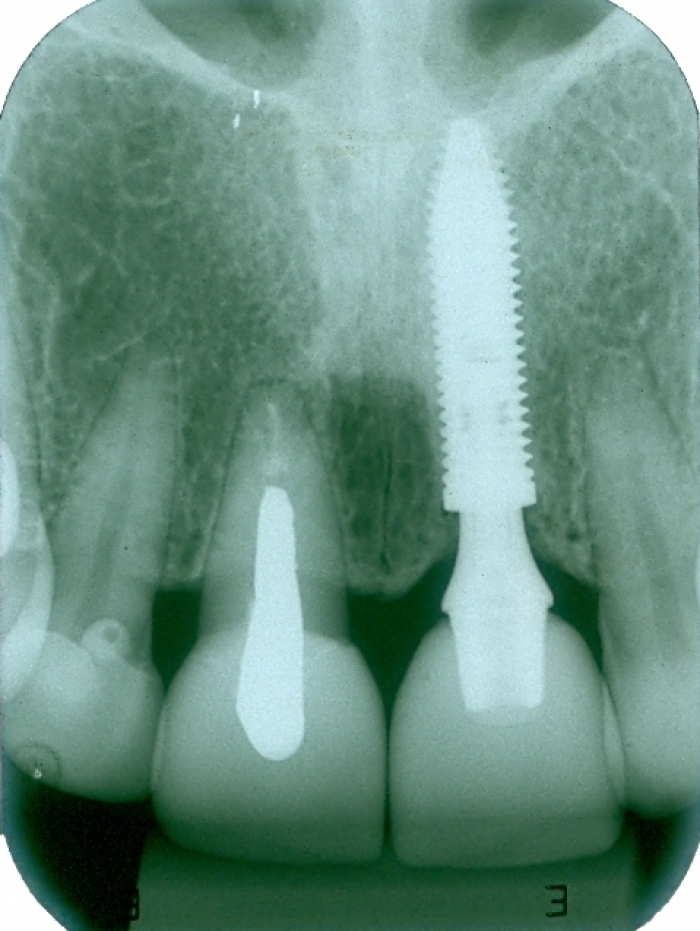

Raio X do implante

Raio X da prótese fixa em porcelana